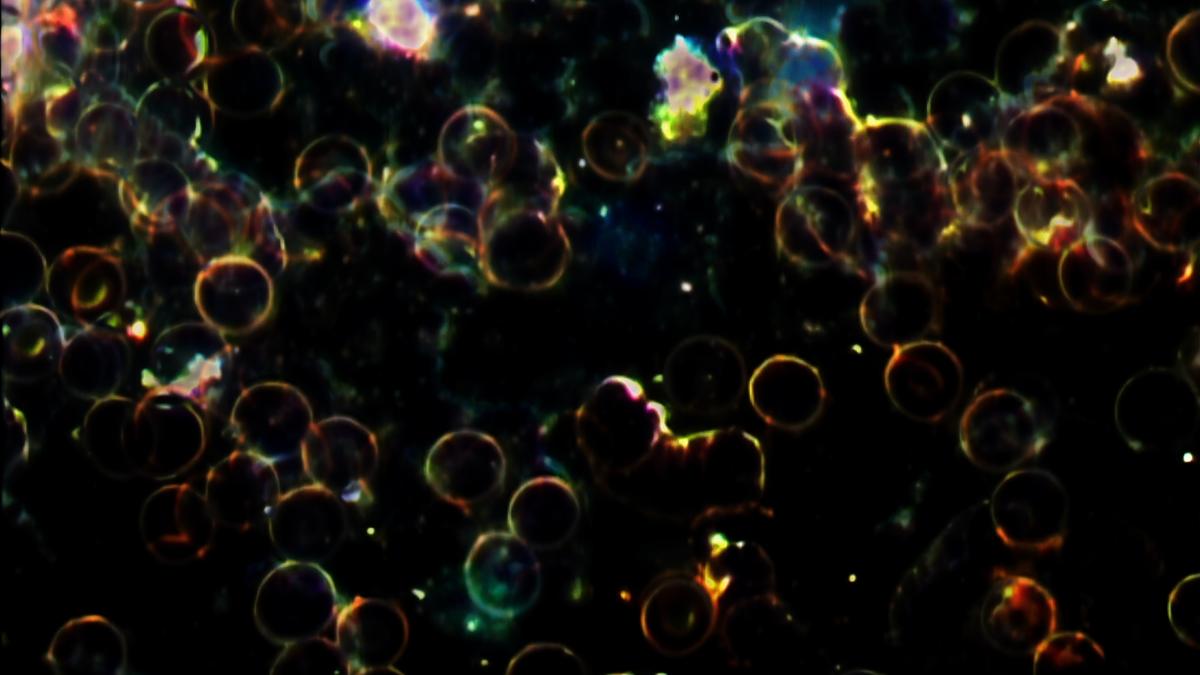

Serginin merkezinde biyolojik verileri soyut portrelere dönüştüren video çalışmaları ve baskılar yer alıyor. Bolten, kendi benliğinin ötesindeki katılımcılardan aldığı kan örneklerini karanlık alan mikroskobu altında görüntüleyerek her bireye özgü görsel parmak izleri yaratıyor. Bu portrelerin her biri, çıplak gözle görülmeyen desenleri açığa çıkaran sanat ve bilimin bir birleşimidir. Böylece sanatçı, kişisel biyolojik verileri görsel bir şiirselliğe dönüştürerek görünmeyeni görünür kılıyor. Bu seri, sanatın tarih boyunca üstlendiği en eski işlevlerden birini, yani gözle görülemeyeni görünür kılma amacını çağdaş bir biçimde yeniden gündeme getiriyor. Aynı zamanda sergi, kimliğin gerçekten nerede bulunduğuna dair temel soruları gündeme taşıyor: Benlik yalnızca zihinde mi, DNA'da mı, yoksa ikisinin karmaşık sentezinde mi? Bolten'in çalışmaları, soyut ile somut arasındaki bu gerilimi görünür kılarak kavramsal gücünü tam da bu ikiliğin arasındaki boşluktan alıyor.